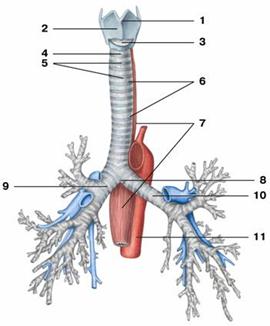

Рис. Трахея и бронхи:

Рис. Трахея и бронхи:

1 — гортанный выступ (кадык); 2 — щитовидный хрящ;

3 — перстнещитовидная связка; 4 — перстнетрахеальная связка;

5 — дугообразные трахейные хрящи; 6 — кольцевые связки трахеи;

7 — пищевод; 8 — раздвоение трахеи;

9 — главный правый бронх; 10 — главный левый бронх;

11 — аорта

Бронхи (bronchi) - органы, выполняющие функцию проведения воздуха от трахеи до легочной ткани и обратно. Различают главные бронхи: правый и левый и бронхиальное дерево, входящее в состав легких. Длина правого главного бронха 1-3 см, левого - 4-6 см. Над правым главным бронхом проходит непарная вена, а над левым - дуга аорты. Правый главный бронх не только короче, но и шире, чем левый, имеет более вертикальное направление, являясь как бы продолжением трахеи. Поэтому в правый главный бронх чаще, чем в левый, попадают инородные тела. Стенка главных бронхов по своему строению напоминает стенку трахеи. Их скелетом являются хрящевые полукольца: в правом бронхе 6-8, в левом - 9-12. Сзади главные бронхи имеют перепончатую стенку. Изнутри главные бронхи выстланы слизистой оболочкой, покрытой однослойным мерцательным эпителием. Снаружи они покрыты соединительнотканной оболочкой (адвентицией).